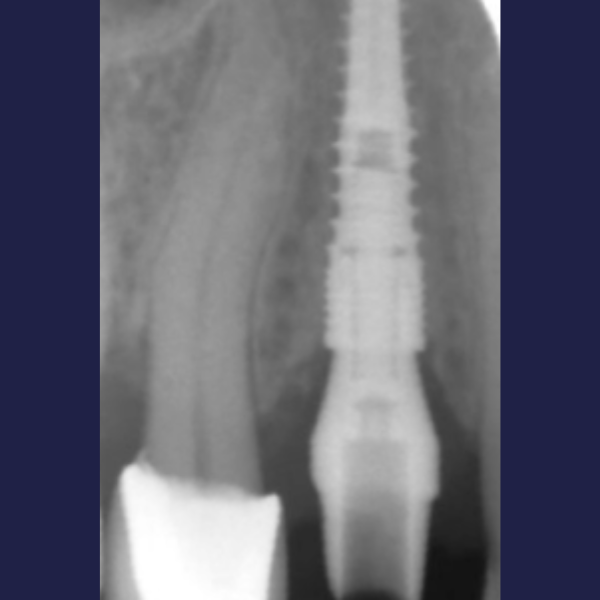

Immediate Dental Implant Placement

Tooth 14 slightly increased mobility, tenderness and bite pain. Suspected root fracture